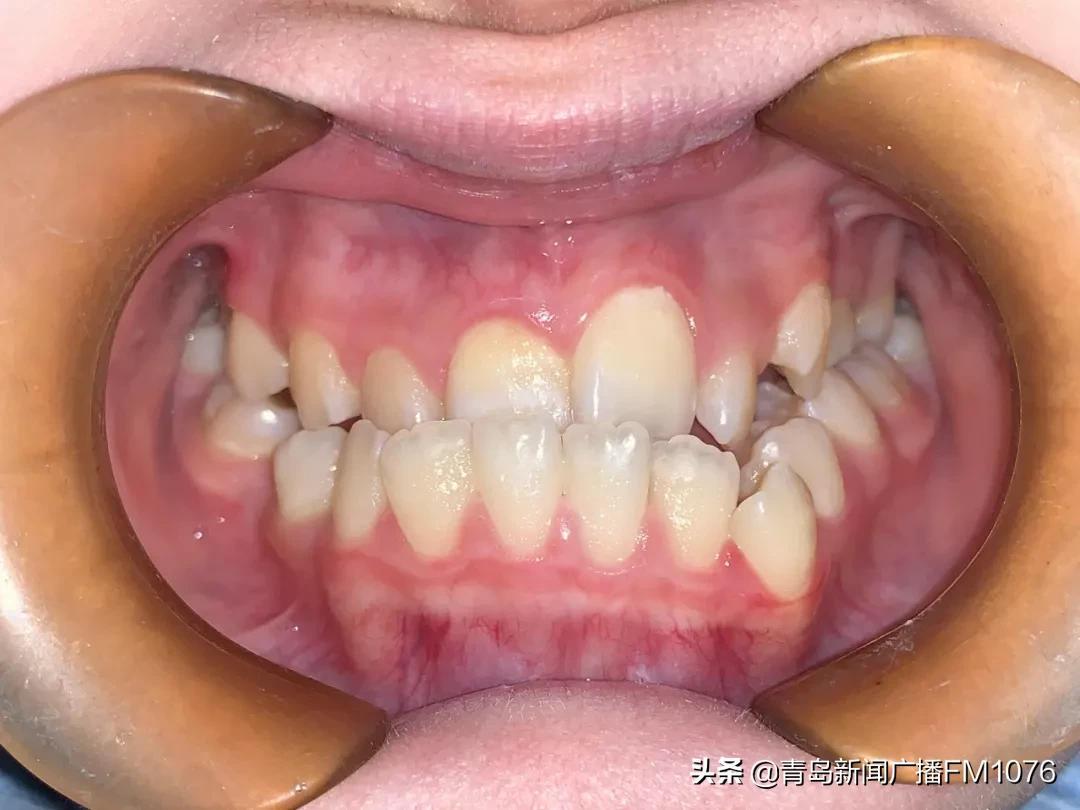

前牙反牙合“地包天”

牙頜畸形的危害主要表現(xiàn)在美觀和功能兩個(gè)方面,但家長(zhǎng)和孩子往往只關(guān)注美觀方面而忽略了功能方面的問(wèn)題。比如后牙鎖牙合這種情況,上下后牙一個(gè)頰向傾斜錯(cuò)位一個(gè)舌向傾斜錯(cuò)位,兩個(gè)牙齒沒(méi)有咬合接觸,雖然有這兩顆牙齒,但沒(méi)有功能,沒(méi)法咀嚼吃飯,這個(gè)后牙鎖牙合牙齒情況現(xiàn)在發(fā)病率很高,并且很容易被家長(zhǎng)和孩子忽視。前牙開(kāi)牙合往往上下牙齒排列挺整齊,但前牙沒(méi)有咬合接觸,也無(wú)法咬合接觸,喪失了前牙切割動(dòng)作的咬合功能,也容易被忽視。對(duì)于孩子的牙齒是不是需要矯治要綜合考慮,必要時(shí)候咨詢一下正畸醫(yī)師的專業(yè)意見(jiàn)。